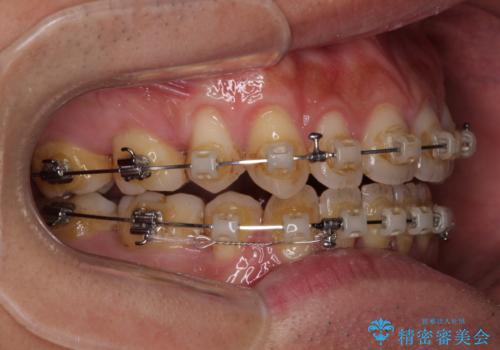

- クリアブラケット

- 2年6ヶ月

- 上下前歯の隙間と口元の出っ張った感じを気にして来院された患者様です。

上下の隙間は舌突出癖によるもので、またその癖により前歯が前方に出ている状態でした。

口元の出っ張りを改善するため、上下左右第一小臼歯4本を抜去し、ワイヤー装置にて矯正治療を行うこととしました。